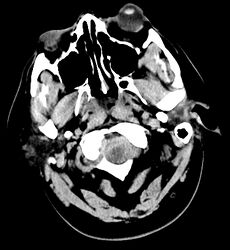

Perimesencephalic subarachnoid hemorrhage

Acute subarachnoid hemorrhage